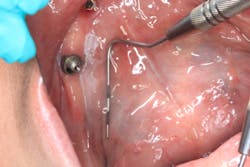

Clinical assessment revealed a white, corrugated lesion lingual to the acrylic of the fixed hybrid prosthesis (figure 2). The lesion measured 5x24 mm and was not able to be scraped off or removed. It was not painful or symptomatic, and no swellings were noted in the sublingual or submandibular lymph node areas (figures 3 and 4).

The unknown etiology of the lesion automatically put it into a category of high-risk leukoplakia, especially since it had just recently manifested and there had been a history of previous biopsy to the area that was diagnosed as precancerous tissue. The patient was seen in my office for prosthesis removal and then referred to an oral surgeon, where she had an excisional biopsy under local anesthesia (figures 5 and 6). The patient's prosthesis was adjusted and appropriate follow-up care was put in place.